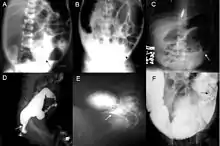

Definitive diagnosis is made by suction biopsy of the distally narrowed segment.[26] A histologic examination of the tissue would show a lack of ganglionic nerve cells. Diagnostic techniques involve anorectal manometry,[27] barium enema, and rectal biopsy. The suction rectal biopsy is considered the current international gold standard in the diagnosis of Hirschsprung's disease.[28]

Radiologic findings may also assist with diagnosis.[29] Cineanography (fluoroscopy of contrast medium passing anorectal region) assists in determining the level of the affected intestines.[30]

Hirschsprung's disease is a congenital disorder of the colon in which certain nerve cells, known as ganglion cells, are absent, causing chronic constipation.[42] In patients with Hirschsprung disease, both myenteric and submucosal plexuses are absent.[43] A barium enema is the mainstay of diagnosis of Hirschsprung's, though a rectal biopsy showing the lack of ganglion cells is the only certain method of diagnosis.